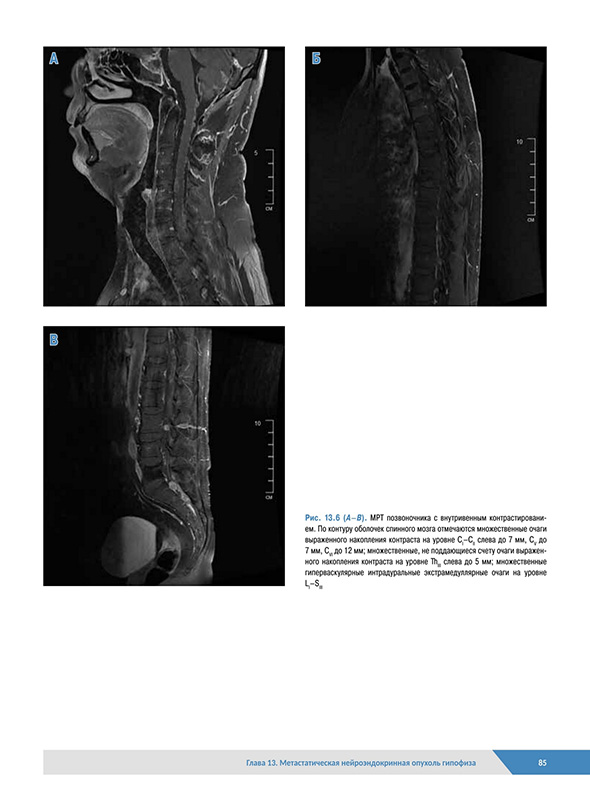

Глава 13. Метастатическая нейроэндокринная опухоль гипофиза

13.4. Лучевая диагностика